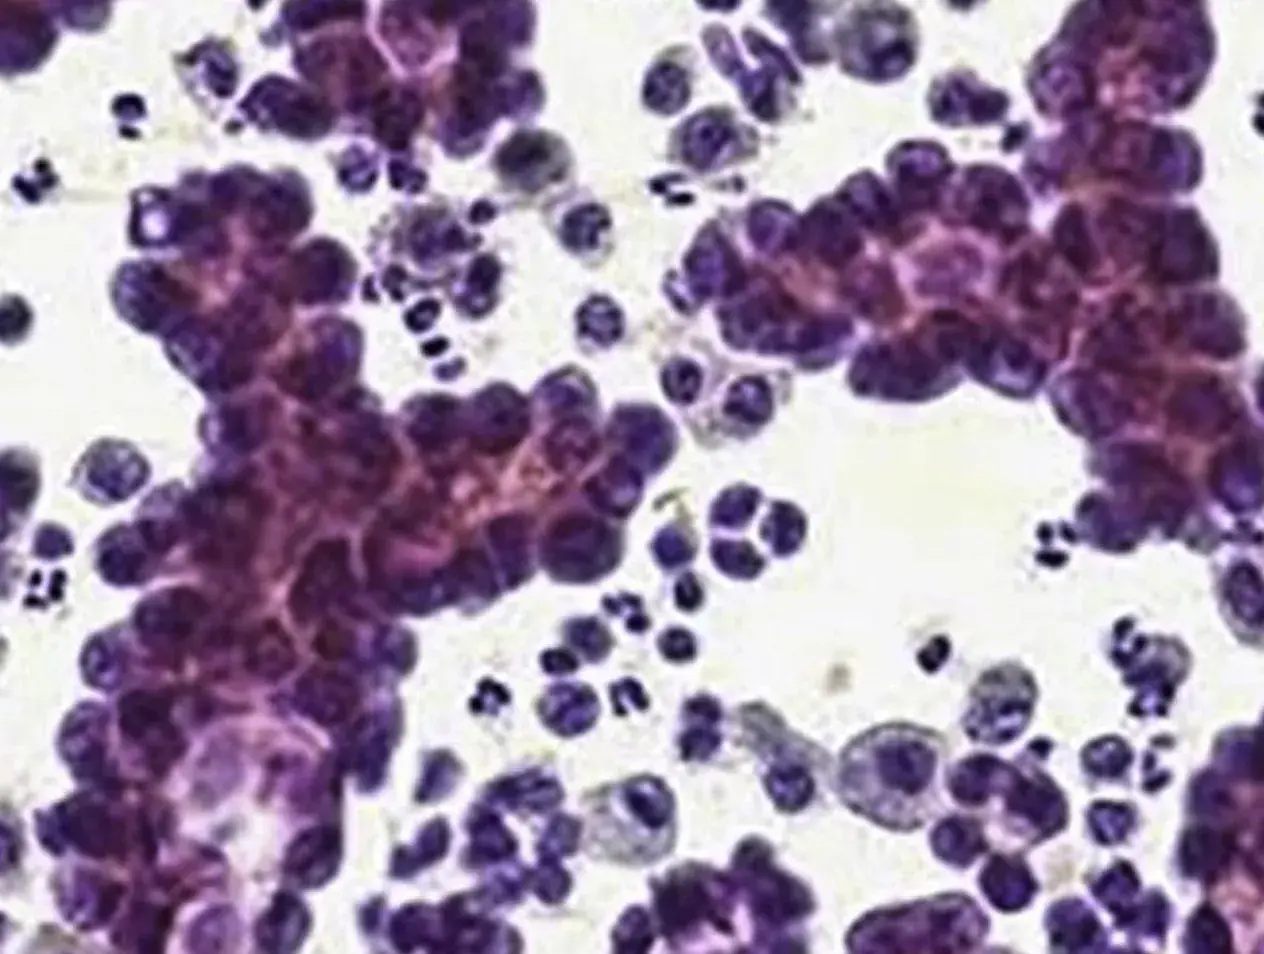

Pic: Papillary thyroid carcinoma in a 34-year old female patient.